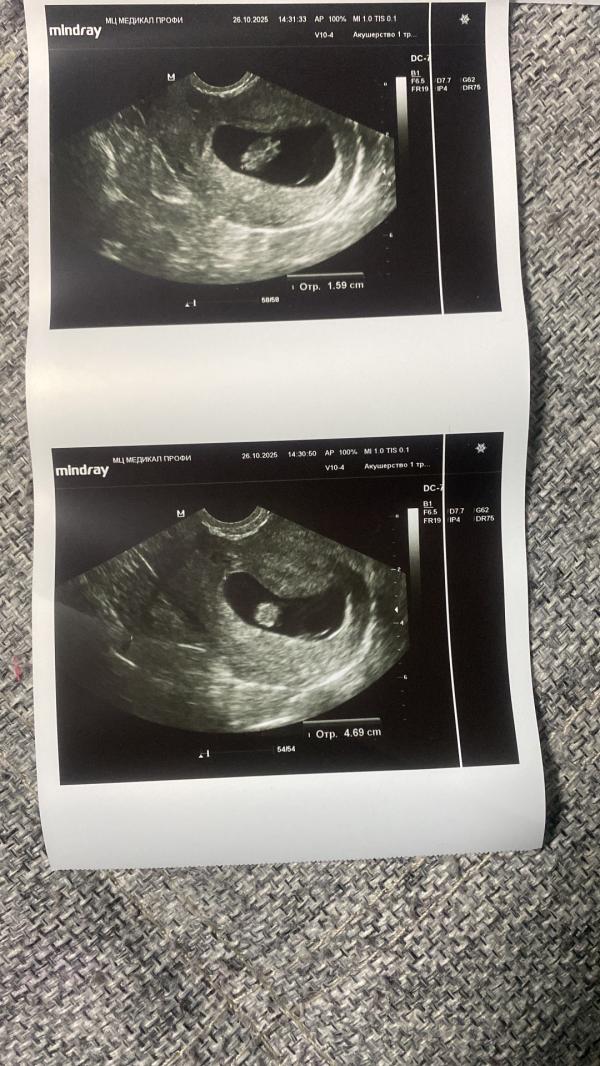

Первое узи это то которое я сделала сейчас, последние 2 фото это узи которое я делала в 7,3 недели . Эта тупорылая курица других слов у меня нет сказала что яйцо не правильной формы и поэтому это угроза прерывания беременности и размеры плода на 6-7 недель . Если что разгон у меня от меняемых до замеров по узи всего в 2 дня был . Плюс даже по ее фото что она сделала тупой поймет что плод значительно вырос от последнего узи . Горе узисты млять)) я конечно завтра схожу до жк с этим узи , но я уверена что все хорошо просто мне попалась реально курица

Ну вот . Я ей говорю оно изначально у меня не круглой формы это раз , два она ставит размеры плода на 6-7 недель . Там последние 2 фото где реально размер на 7,3н было . То есть у нее еще и руки из жопы растут . На фото видно же что вырос от последнего узи

Ну вы внимательно посмотрите оно изначально у меня не круглое то